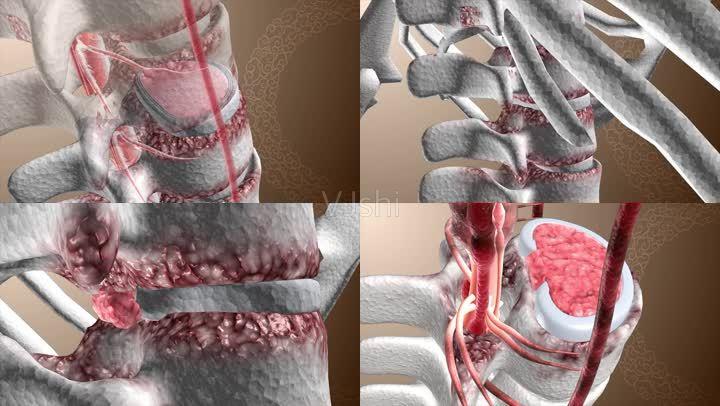

骨二科邓强主任团队杨镇源副主任医师完成甘肃省首例镜下纤维环缝合术

简单的说:膨出和突出最大的区别在于纤维环是否已经破裂,如果没有破裂